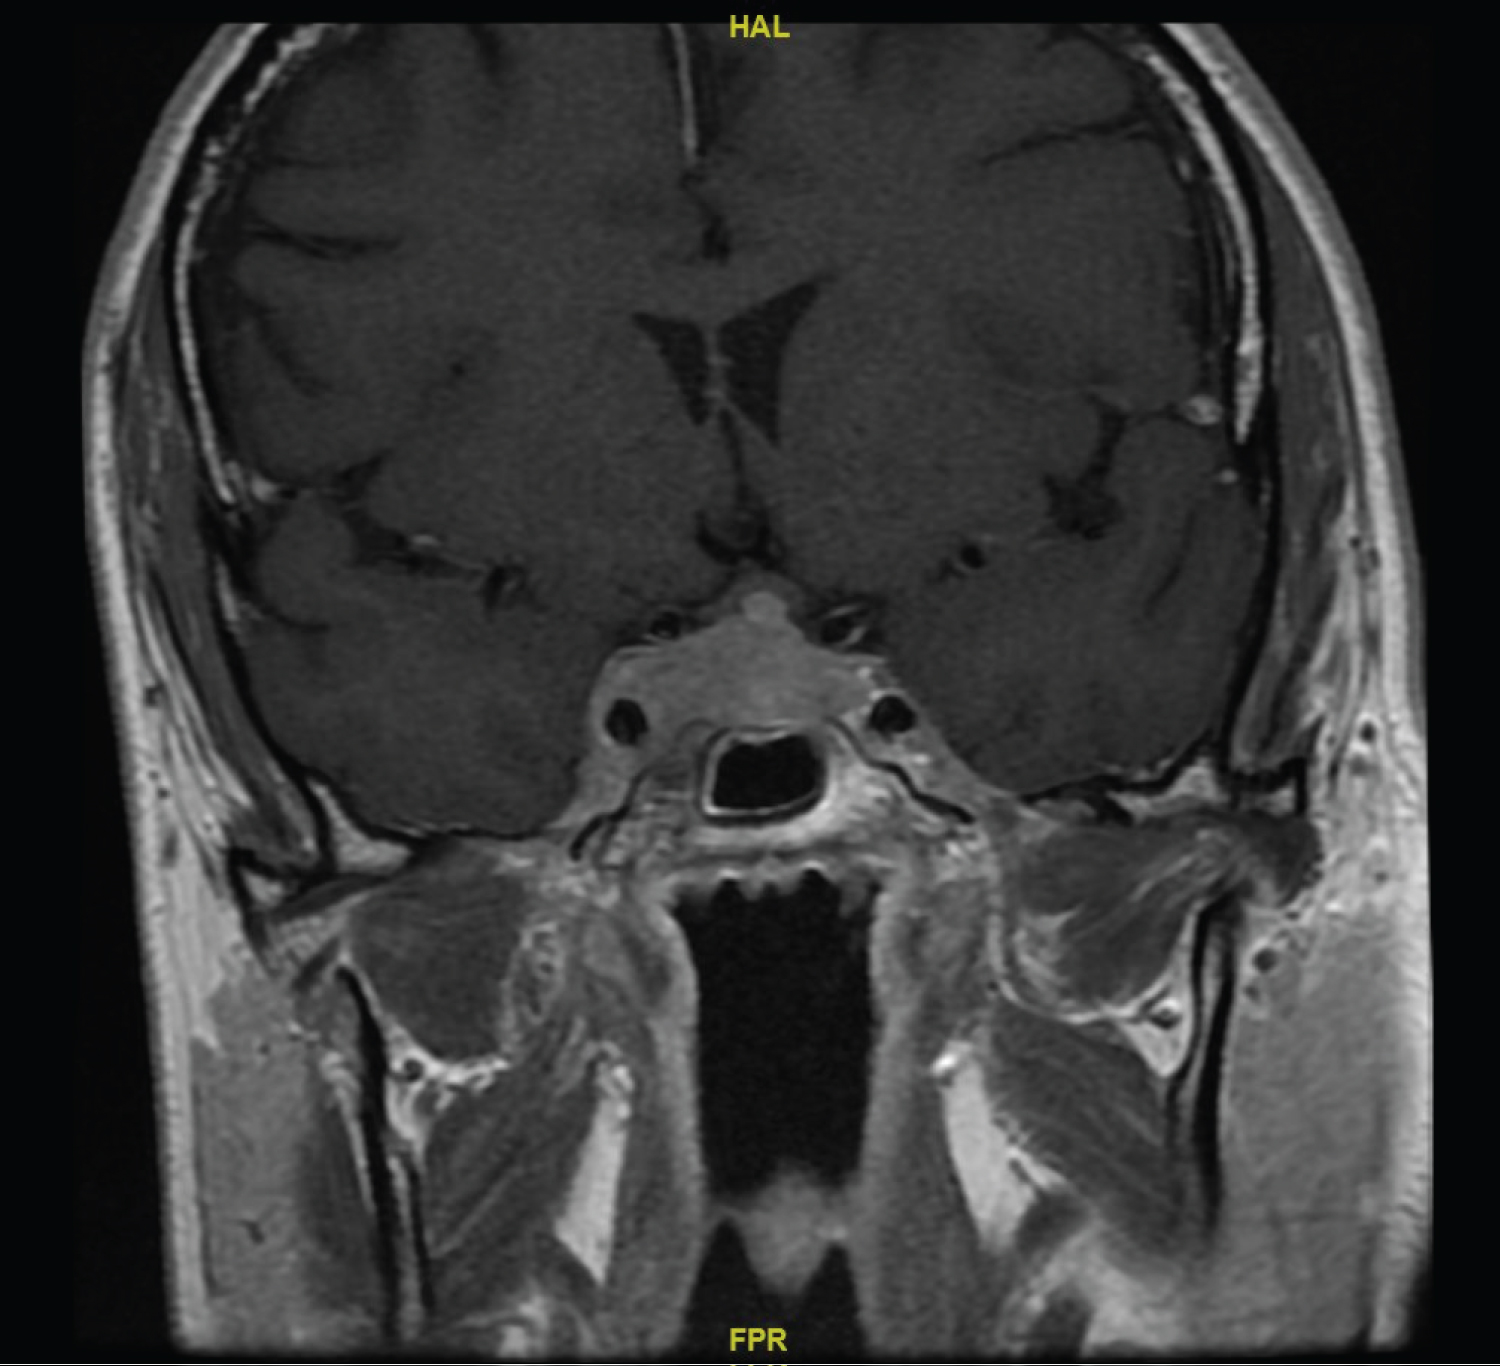

CT head showed no obvious intracranial findings in the brain or pituitary fossa. Lumbar puncture showed raised cerebrospinal fluid (CSF) protein (0.6 g/L) with normal glucose (3.5 mmol/L); no organisms were seen on CSF microscopy or gram staining. Mature lymphocytes were present in the CSF with no evidence of clonality on immuno phenotyping. CSF analysis by PCR excluded Epstein Barr Virus, Cytomegalovirus, Human Herpes virus 6 and Human Herpes virus 8. Magnetic Resonance Imaging (MRI) head with contrast showed a 13 × 37 × 13 mm homogeneously-enhancing sellar mass which invaded the right cavernous sinus with mild displacement of the optic chiasm (Figure 1a). Pituitary function was normal. A CT CAP had shown the widespread lymphadenopathy was stable in size compared with previous imaging from initial diagnosis of MZL. A staging whole body fluorodeoxyglucose (FDG)-positron emission tomography (PET)CT scan showed an FDG-avid lesion with a maximum standardized uptake value (SUVmax) of 11.6 g/ml in the cavernous sinus together with widespread supra- and infra-diaphragmatic FDG-avid nodal disease with splenic involvement.

Figure 1a: MRI showing right-sided cavernous sinus invasion at presentation. View Figure 1a

MRI head 6 months after chemotherapy showed a significant reduction in the size of the mass in the pituitary fossa which no longer compressed cranial nerves. Cranial nerve palsies had also resolved. Before the most recent review, MRI head 21 months following chemotherapy showed resolution of the sellar mass (Figure 1b). At this time CT CAP showed complete resolution of supra- and infra- diaphragmatic lymphadenopathy. Furthermore, full blood count values were within reference ranges and endocrine status was grossly normal. This suggested disease remission.

Figure 1b: Resolution of cavernous sinus mass after chemotherapy. View Figure 1b